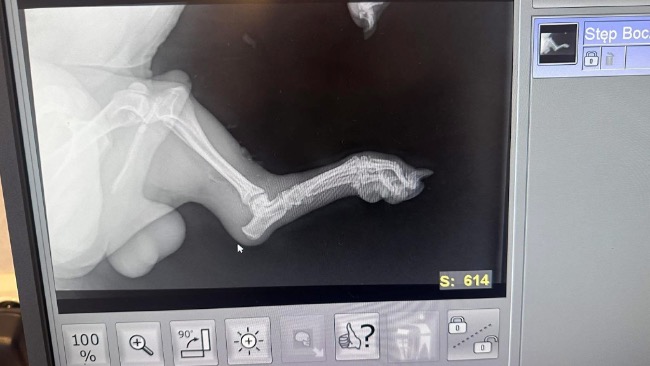

Misio z rowu walczy o powrót do sprawności. Dzięki ludziom, którzy nie przeszli obojętnie psiak żyje… Czeka go skomplikowana operacja łapki. Bardzo prosimy o pomoc w opłaceniu operacji.